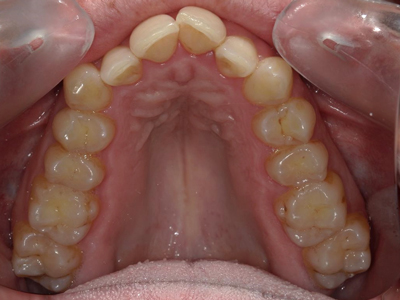

Présentation cas n°1 :